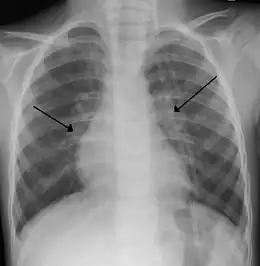

- La radiographie pulmonaire montre une opacité diffuse de la trame pulmonaire, une augmentation de la taille des espaces intercostaux et un abaissement des coupoles diaphragmatiques.